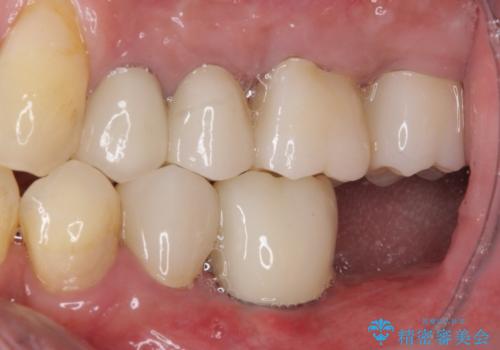

- 一度治療を終えたものの、奥歯へインプラントの追加を希望された患者様です。

最後臼歯部にインプラントを1本追加埋入し、2歯連結のクラウンにて補綴治療を行うこととしました。